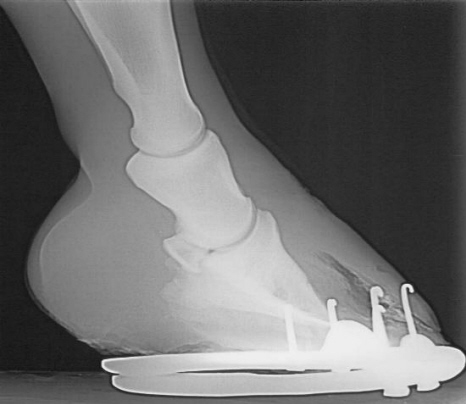

Lose Wand